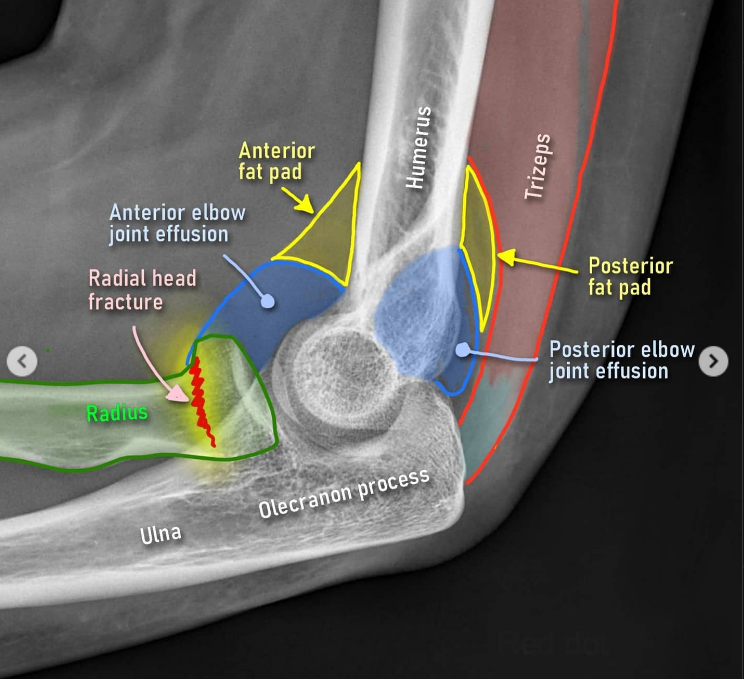

Fat pad sign (signo de la almohadilla grasa)

¿Qué indica el signo de la almohadilla grasa en Rx lateral de codo? (teórico clínico | poca relevancia)

La grasa periarticular normalmente está pegada al hueso (anterior: invisible o apenas visible; posterior: invisible)

Derrame articular → grasa se desplaza/levanta → visible como triángulo radiolúcido

Fat pad anterior elevada: inespecífica pero sugiere derrame

Fat pad posterior visible: SIEMPRE patológica → derrame → sospechar fractura oculta (especialmente cabeza del radio)

En niños con Rx "normal" pero fat pad positivo → tratar como fractura hasta probar lo contrario